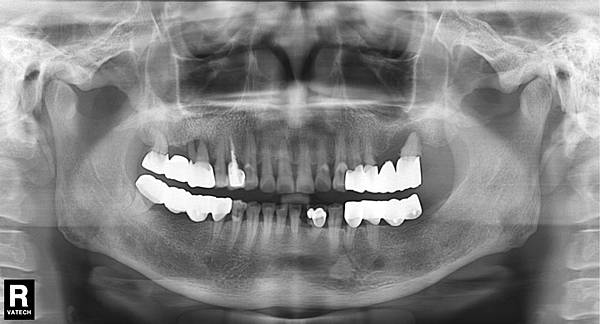

人工植牙摩擦力固持牙冠(friction retention crown)

人工植體鎖入人體後, 接下來就是進行上部牙套的製作, 就如同建築物開始建造地上物一般, 牙套製作方式大致分為四種1.黏著固定式 2.螺絲固定式3.客製化支台+牙套 4.摩擦力固持牙套, 而其中又以磨擦力固持牙套為本診所的特點, 以下介紹摩擦力固持牙冠, 此種作法發明人為鶴卷技工師, 相關網站及文獻如下: